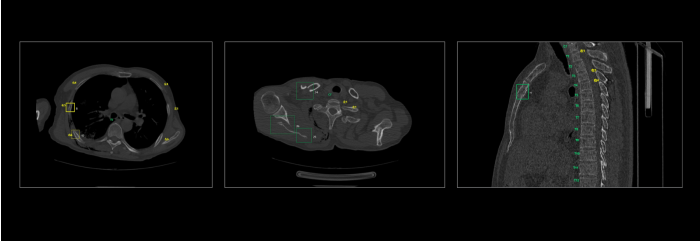

联影智能CT骨折智能分析系统具备“精确定位,秒级骨折检出,直观提示病灶,精细优化工作流”等一系列特点。基于深度学习的方法,自动完成肋骨、椎骨定位与计数,智能完成肋骨、椎骨、锁骨、肩胛骨、胸骨骨折检出与分类。同时,系统还提供MPR三视图、VR图、3D MIP、CPR、SCPR图像的全肋骨展开图、局部动态图等多种阅片视图,一键自动呈现骨折最佳视角,让骨折一目了然,细微骨伤“无处遁形”,辅助医生快速、高效、精准地完成骨折的诊断,避免错诊和漏诊。